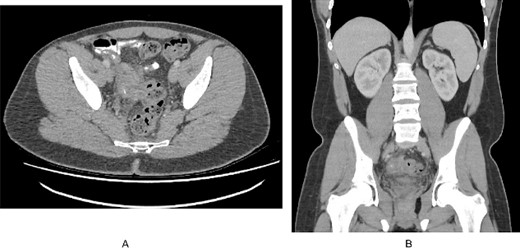

A 22 years old male with no prior medical or surgical history presented to the emergency department with 3 weeks history of lower abdominal pain and rectal discomfort. The pain was noted to be more suprapubic rather than the right iliac fossa but his abdomen was soft with no features of peritonism. He denied fevers, nausea or vomiting, or changes to bowel habits. There was no family history of bowel cancers or inflammatory bowel disease. His observations on admission were unremarkable. Pathology testing revealed a white cell count of 8.30 x 109/L and a c-reactive protein of 22 mg/L. An initial ultrasound of the abdomen visualized a non-compressible tubular structure measuring 9 mm in the right iliac fossa with 4.4 ml of surrounding free fluid and prominent lymph nodes. Given the atypical history for appendicitis, a computed tomography of the abdomen and pelvis was performed which demonstrated significant inflammatory change close to the terminal ileum extending to the right pelvic side wall with a calcific focus possibly representing an appendicolith (Fig. 1). The actual appendix was not seen as a distinct entity and the actual terminal ileum itself was not thickened.

(A). Axial slice of a CT abdomen/pelvis in the portovenous phase demonstrating an inflammatory mass in the pelvis associated with the right pelvic side wall, with a calcific focus. (B). Coronal slice of the CT demonstrating the relation of the inflammatory mass within the pelvis.